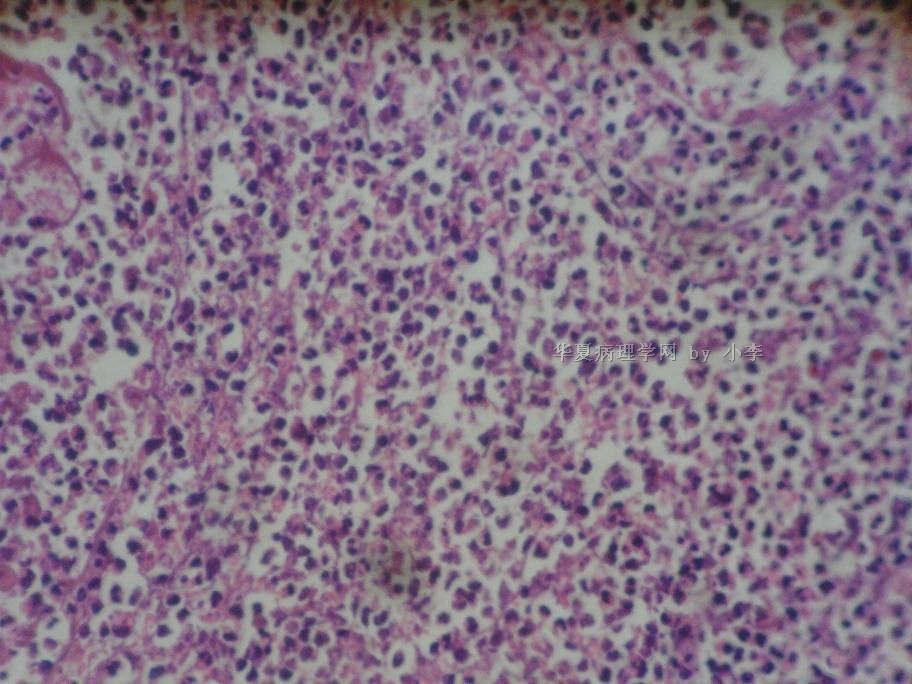

睾丸炎?

姓    名: ××× 性别:  男 年龄: 46岁

• 睾丸炎?图1

图1

首先考虑精子肉芽肿

慢性肉芽肿性炎

肉芽肿性睾丸炎

精子肉芽肿